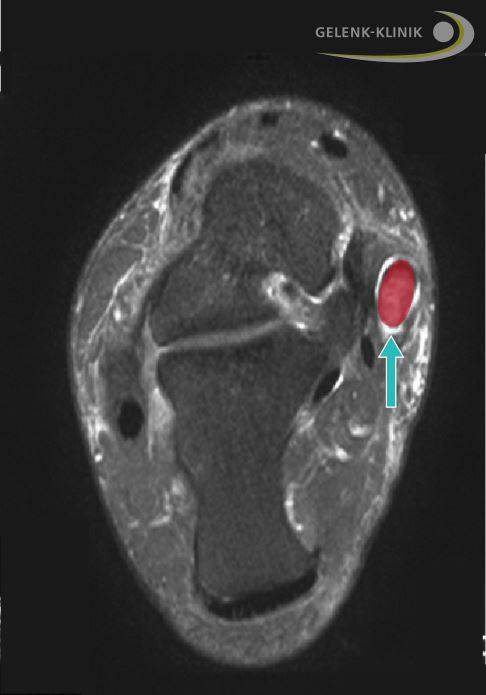

Bei einer beginnenden Fehlstellung können Eingriffe an der Tibialis-posterior-Sehne sinnvoll und ausreichend sein. Häufig ist die Sehnenhülle der Tibialis-posterior-Sehne entzündlich verändert (Tenosynovitis). In einer minimalinvasiven Sehnenoperation kann der Arzt die entzündeten Bereiche der Sehnenhaut beseitigen. Die Entfernung der entzündeten Bereiche verhindert ein weiteres Voranschreiten der Sehnenentzündung. Im Bedarfsfall kann die Tibialis-posterior-Sehne in geschwächten Bereichen leicht verkürzt und neu vernäht ("gerafft") werden.

Sehnentransplantation: Einsatz einer körpereigenen Sehne

Bei weitergehender Schädigung kann der Operateur die Tibialis-posterior-Sehne ersetzen, zum Beispiel durch die Transplantation einer körpereigenen (autologen) Sehne an den Fußinnenrand. Für den Transfer eignet sich besonders die Sehne des langen Zehenbeugers (Musculus flexor digitorum longus). Dieser Sehnentransfer ersetzt nur teilweise die Funktion der ursprünglichen Tibialis-posterior-Sehne, sodass knöcherne Begleiteingriffe notwendig sind. Die verringerte Zehenbeweglichkeit nehmen unsere Patienten erfahrungsgemäß ohne Probleme in Kauf und empfinden diese als wenig einschränkend. Sie profitieren mit einer verbesserten Stabilität des Fußgewölbes und leiden deutlich weniger unter Schmerzen und Gangveränderungen.